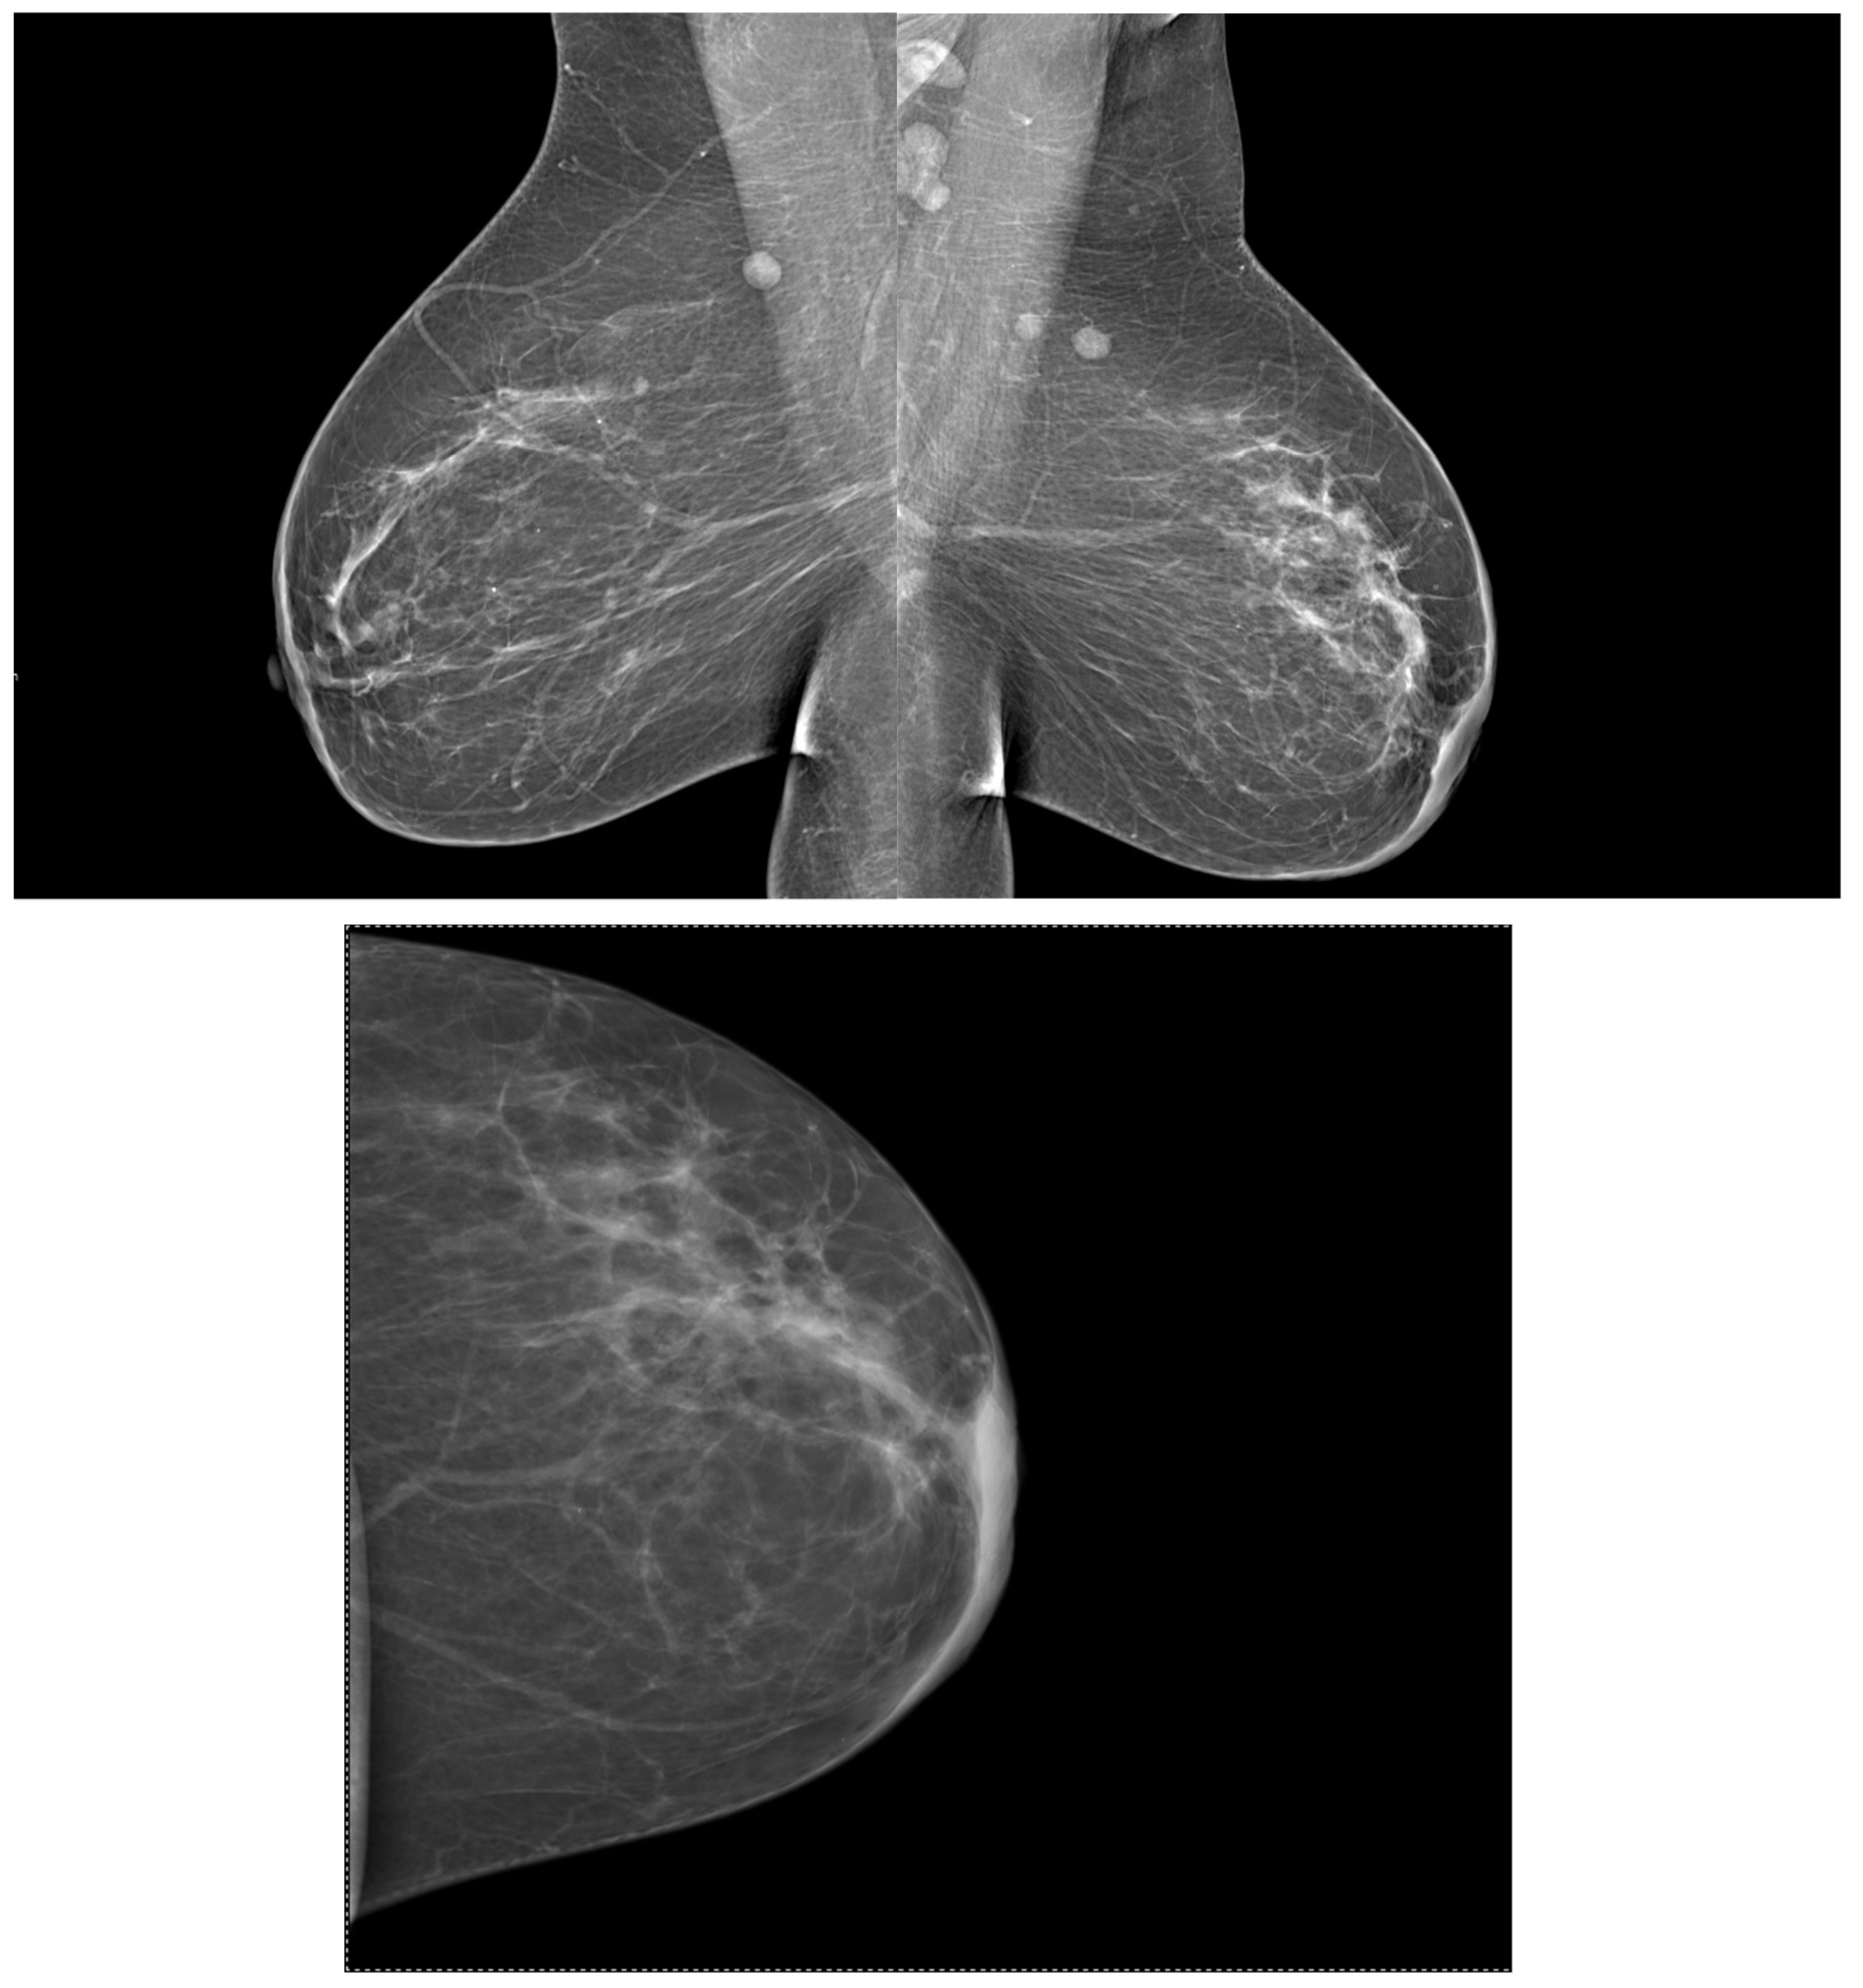

2.2. Mammography (MG)

3.5. Correlations between Molecular Subtypes of BC and Their Mammographic Features

3.6. Correlations between Molecular Subtypes of BC and Their Ultrasonographic Features

- Shaikh, S.; Rasheed, A. Predicting Molecular Subtypes of Breast Cancer with Mammography and Ultrasound Findings: Introduction of Sono-Mammometry Score. Radiol. Res. Pract. 2021, 2021, 6691958. [Google Scholar] [CrossRef] [PubMed]

- Li, N.; Gong, W.; Xie, Y.; Sheng, L. Correlation between the CEM imaging characteristics and different molecular subtypes of breast cancer. Breast 2023, 72, 103595. [Google Scholar] [CrossRef]

- Ian, T.W.M.; Tan, E.Y.; Chotai, N. Role of mammogram and ultrasound imaging in predicting breast cancer subtypes in screening and symptomatic patients. World J. Clin. Oncol. 2021, 12, 808–822. [Google Scholar] [CrossRef]